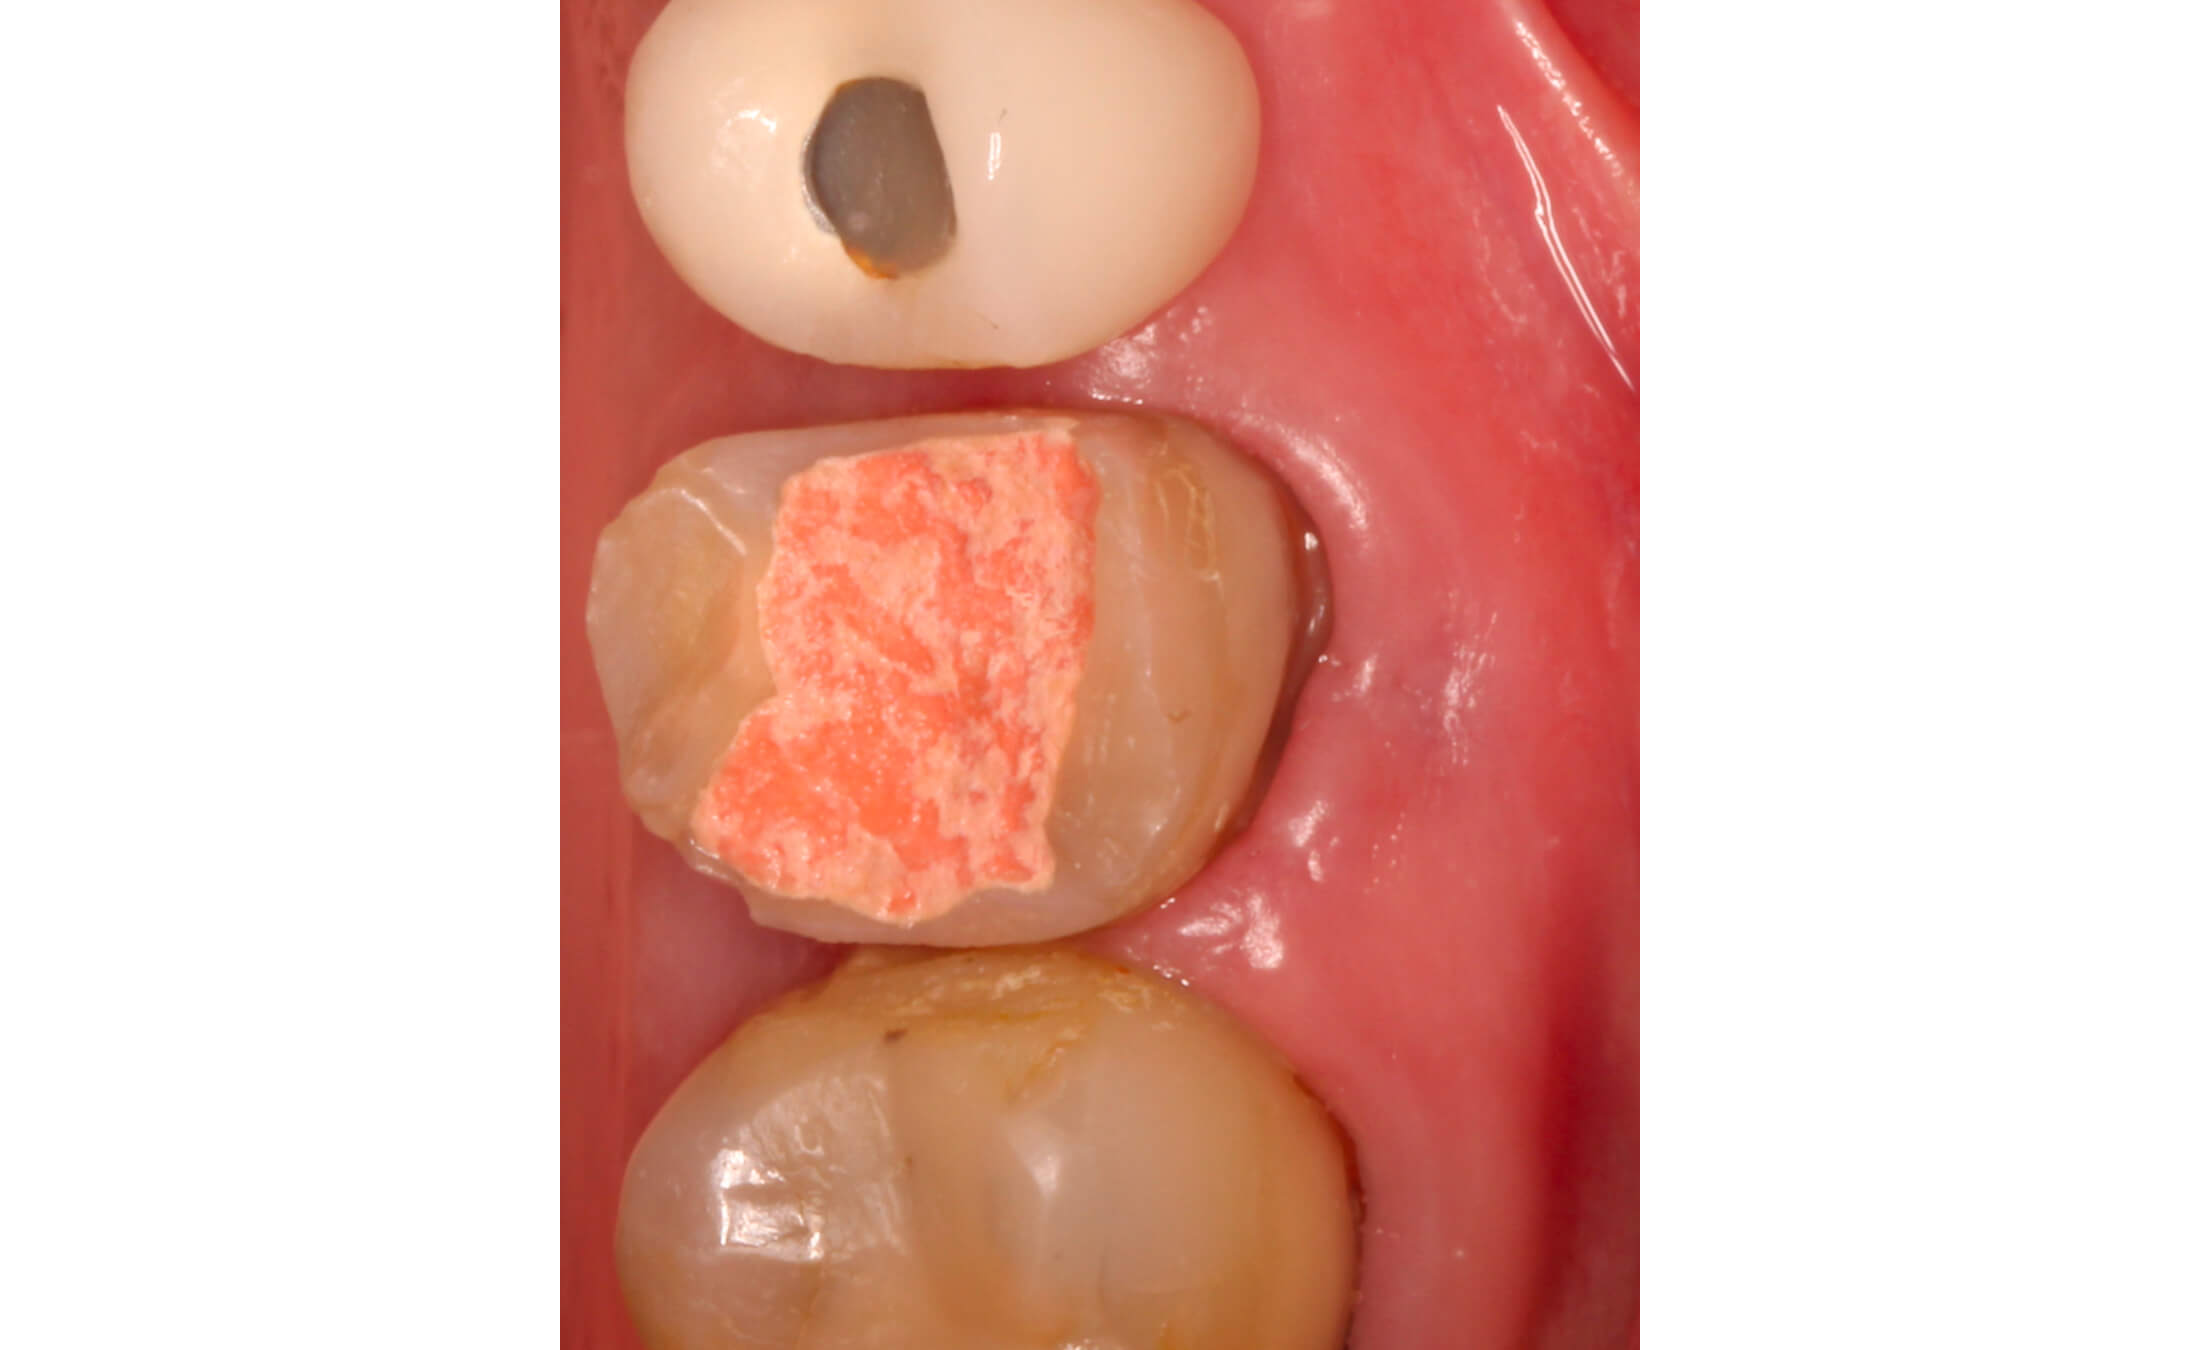

3. By the two-week recall visit, complete closure of the sinus tract was observed, demonstrating favorable resolution of the periradicular inflammation. (Image 6)

4. By the two-week recall visit, complete closure of the sinus tract was observed, demonstrating favorable resolution of the periradicular inflammation. (Image 7,8)